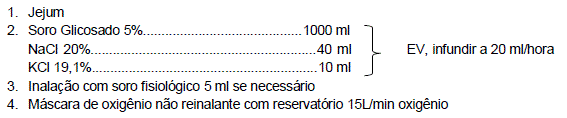

Lactente masculino, 2 meses de idade, nascido de termo, parto vaginal, sem intercorrências até o momento, está sendo reavaliado na retaguarda de um Pronto-Socorro. Há 4 dias iniciou quadro de coriza hialina e tosse, e há um dia evoluiu com desconforto respiratório. Apresentou febre de até 38,6°C apenas no primeiro dia de história do quadro atual. O paciente deu entrada há cerca de 10 horas e está com a seguinte prescrição: Peso 4,8 kg

No momento da sua reavaliação, o paciente está em regular estado geral, hidratado, pálido, com ausculta pulmonar com sibilos e crepitações difusas, tiragens subdiafragmática, intercostal e de fúrcula, batimento de asas nasais, FR: 88 ipm, saturação de oxigênio 90% com oferta de O2, FC: 180bpm, PA: 78/40mmHg. Sem alterações das propedêuticas cardíaca e abdominal. Tempo de enchimento capilar de 2 segundos, pulsos normais, sem edema.

Com relação ao suporte hídrico prescrito, está correto afirmar que: